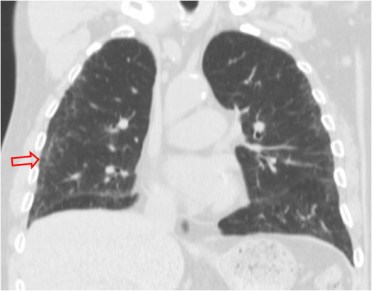

SIGNO DE LAS ALAS DE MARIPOSA INVERTIDAS

La presencia de infiltrados alveolares de disposición periférica y bilateral, respetando las regiones perihiliares, provoca una imagen opuesta a la del signo de las alas de mariposa. Este hallazgo se ve en la neumonía eosinófica.

La imagen de la TC muestra los focos de condensación alveolar periféricos y bilaterales, con predominio en el pulmón derecho.